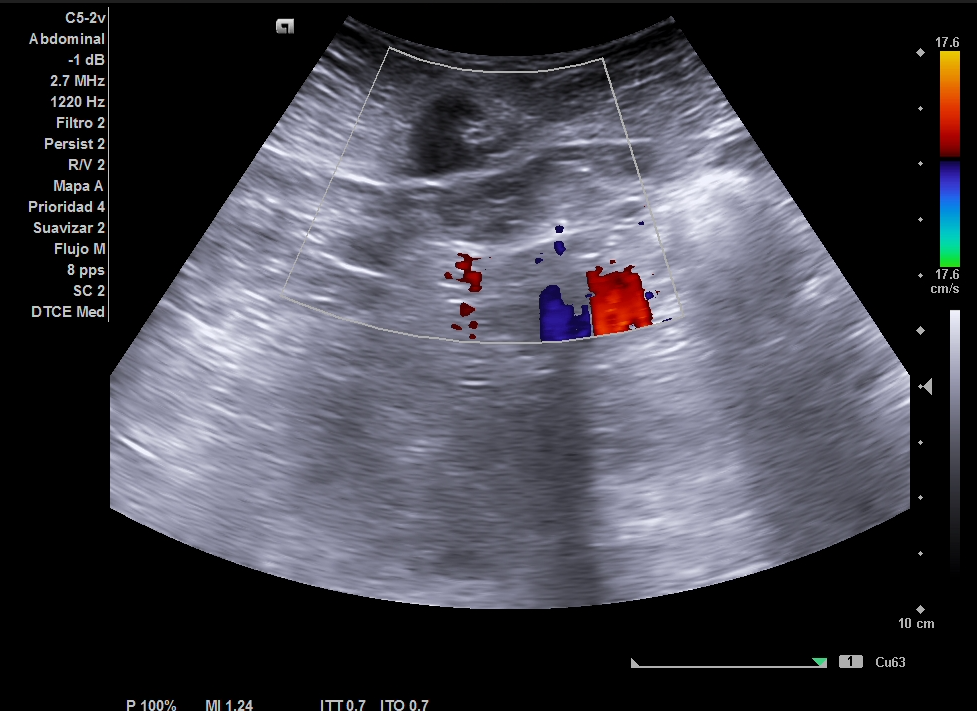

Ecografía clínica partes blandas y abdominal en Centro de Salud: dos nódulos subcutáneos hipoecogénicos, heterogéneos, lobulados y de bordes irregulares (16 x 18 mm), no vascularizados. Abdomen: sin signos patológicos relevantes ni Ascitis ni líquido en Douglas no adenopatías retroperitoneales. Completamos estudio de nódulos sospechosos de malignidad con tomografía abdominal y ecografía de partes blandas reglada.

Ecografía reglada de partes blandas: Nódulos subcutáneos e intrabdominales sospechosos de malignidad. La tomografía abdominal describe múltiples implantes sólidos peritoneales y en pared abdominal, compatibles con metástasis.